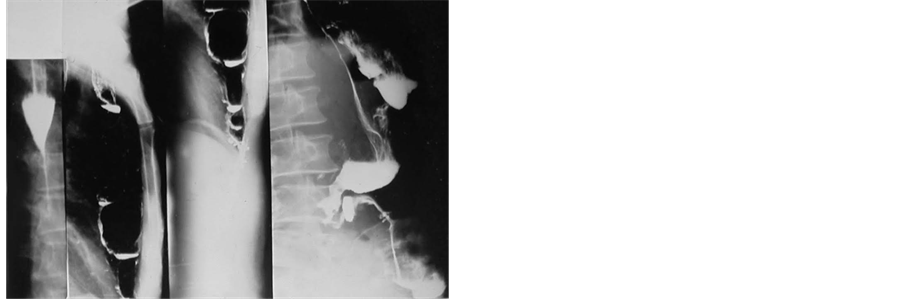

1) After chemical trauma, gastric emptying disturbance was the most common complication, which required to be managed whithin 2 month. Nine of such 17 patients underwent limited Billroth I resection with or without gastrostomy, but never earlier then 6 weeks after injury (Figure 1). In 3 others middle (with gastric reanas- tomosis) proximal or total gastrectomy were performed. The remaining 5 cases were transferred with GEA or Billroth II resection and established esophageal stricture. In these unfavorable condition for esophageal reconstruction, the first step was conversion of previous gastric operation into Billroth I one (Figure 2). In all 17 cases, except one, for associated and intractable esophageal sticture (Figure 3) a substernal by-pass with isoperistaltic transverse colon segment was done, implanted high in the gastric stump.

Figure 1. Types of management in corrosive gastric lesions.

Figure 2. Aspect of antecolic GEA converted in Billoth I anastomosis.

Figure 3. Aspect of substernal colonic by-pass done for the filiform esophageal stricture.

Figure 4. Aspect of Billroth I stump connected with a colonic graft.

Figure 5. Aspect of substernal transverse colon segment with pharyngocolostomy.